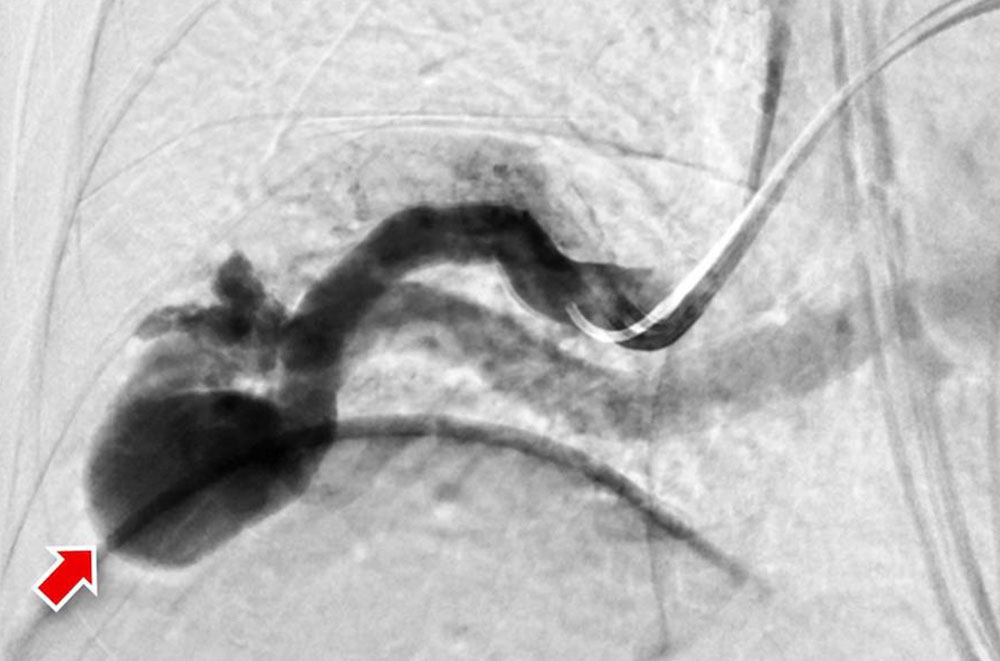

Digital subtraction angiography (DSA) is a radiological procedure for direct imaging of blood vessels via injected contrast medium. In this procedure, a series of several X-ray images are taken of the same location before and after iodine-containing contrast medium is injected into the vascular system via a thin catheter. The first image (without contrast medium) is digitally subtracted from each subsequent image with contrast medium. Thus, subtracting images without from images with contrast medium creates new subtracted images in which only the fresh injected contrast medium flowing into the vascular system is displayed. Surrounding structures such as soft tissue and bones are thus rendered seemingly “invisible” (subtracted). Depending on the localization of the vascular malformation, catheter-assisted imaging is performed via an arterial access (e.g., AVM on a limb) or via a venous access (imaging of pulmonary AV fistulas). In the case of arterial accesses, the puncture site is provided with a pressure dressing after DSA and catheter removal.

Fast-flow malformation (AVM and AVF): The exact anatomical morphology and the hemodynamics of a fast-flow vascular malformation can be very accurately analyzed with the use of DSA. The most important feature of a fast-flow vascular malformation is the immediate contrast filling of the draining veins via the nidus. Angiographically, fast-flow malformations can be categorized into four subtypes:

• In type II there is a dominant drainage vein, this can be aneurysmal.

In advanced disease, the incoming and outgoing vessels are also increasingly tortuous and dilated. In some cases, flow-related aneurysms are formed.